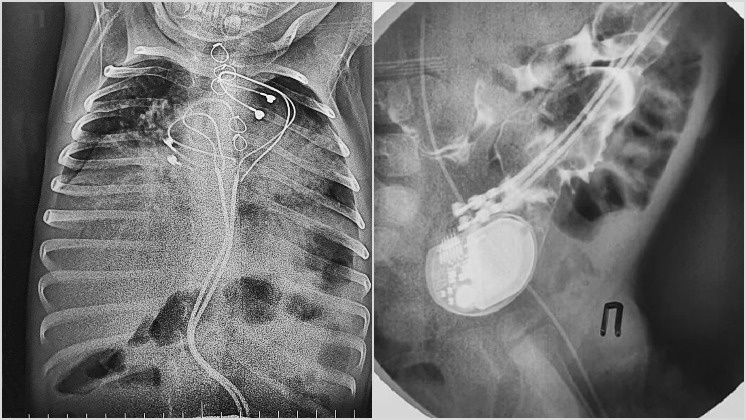

Новосибирские хирурги провели уникальную операцию совсем маленькому пациенту. Врачи спасли трехлетнего малыша, жизни которого угрожал кардиостимулятор. Подробности рассказали в группах «НМИЦ им. академика Е. Н. Мешалкина» и «Новосибирская Областная больница» в социальной сети «ВКонтакте». Ребенок появился на свет с редкой формой аритмии, которая встречается один раз на 25 тысяч новорожденных. Для того, чтобы малыш смог жить, на второй день после рождения, ему имплантировали кардиостимулятор. Спустя три года мальчик попал в одну из больниц Барнаула с высокой температурой и кишечной непроходимостью. Обследование показало невероятное: стимулятор, проникнув сквозь мышцы, мигрировал в кишечник. При этом аппарат продолжал работать и задавать нужный ритм сердцу ребенка. Кардиостимулятор не покинул организм естественным путем благодаря проводам и электродам, которые тянулись за ним от сердца. Ситуация была крайне опасна для жизни ребенка, поэтому его срочно доставили санавиацией в Новосибирск.

Спустя три года мальчик попал в одну из больниц Барнаула с высокой температурой и кишечной непроходимостью. Обследование показало невероятное: стимулятор, проникнув сквозь мышцы, мигрировал в кишечник. При этом аппарат продолжал работать и задавать нужный ритм сердцу ребенка. Кардиостимулятор не покинул организм естественным путем благодаря проводам и электродам, которые тянулись за ним от сердца.

Ситуация была крайне опасна для жизни ребенка, поэтому его срочно доставили санавиацией в Новосибирск. За дело взялись опытные хирурги. Они извлекли кардиостимулятор, очистили кишечник от спаек, а в грудную клетку установили новый стимулятор. Спустя десять дней мальчика выписали в удовлетворительном состоянии.